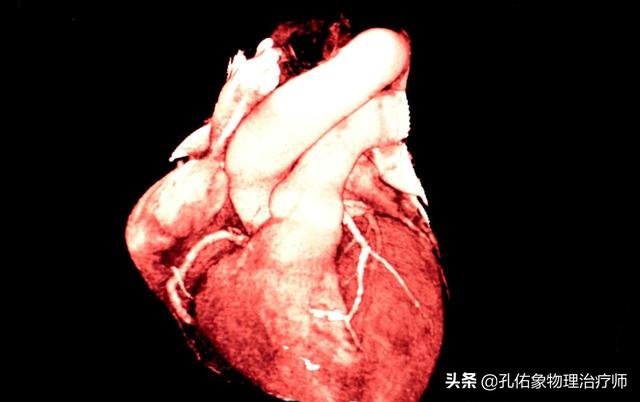

La maladie coronarienne fait principalement référence à la cardiopathie coronarienne athéroscléreuse, qui est une maladie cardiaque due à l'athérosclérose des artères coronaires, qui entraîne un rétrécissement ou une occlusion des artères coronaires, avec pour conséquence l'ischémie, l'hypoxie et la nécrose des cellules du muscle cardiaque. Pour diagnostiquer une maladie coronarienne, il est nécessaire de combiner les symptômes cliniques, les tests de laboratoire, l'électrocardiogramme, la tomodensitométrie coronarienne, la coronarographie et d'autres examens complets.